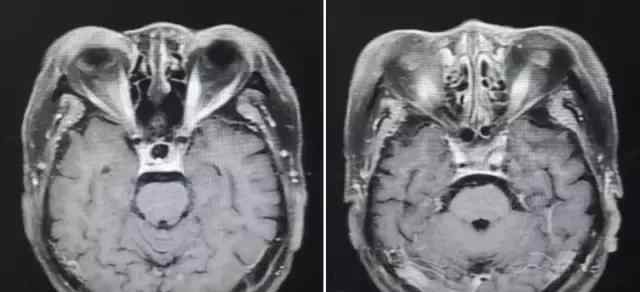

住院后查MRI,汇报上说沒有出现异常,大伙儿从下面的图中看到了哪些?

图7 T1提高相

回答:右眼内直肌、外直肌、下直肌较右边增大增粗。这一主要表现实际上在T1、T2上也可以见到,这儿没放图了。

的确,这一影象上海绵窦变病并不是十分显著,左边海绵窦稍微较右边提高稍显著,可是并不是十分毫无疑问;左边颈内动脉好像比右边稍粗,都不十分毫无疑问。可是发觉眼外肌增大增粗后,炎症性、恶性肿瘤侵润有关病症概率相对性很大,而机械设备挤压的概率就变小。